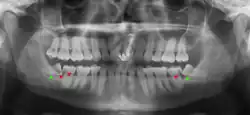

Impacted wisdom teeth are classified by their direction of impaction, their depth compared to the biting surface of adjacent teeth and the amount of the tooth's crown that extends through gum tissue or bone. Impacted wisdom teeth can also be classified by the presence or absence of symptoms and disease. Screening for the presence of wisdom teeth often begins in late adolescence when a partially developed tooth may become impacted. Screening commonly includes a clinical examination as well as x-rays such as panoramic radiographs.

If the tooth cannot be assessed with clinical exam alone, the diagnosis is made using either a panoramic radiograph or cone-beam CT. Where unerupted wisdom teeth still have eruption potential several predictors are used to determine the chance of the teeth becoming impacted. The ratio of space between the tooth crown length and the amount of space available, the angle of the teeth compared to the other teeth are the two most commonly used predictors, with the space ratio being the most accurate. Despite the capacity for movement into early adulthood, the likelihood that the tooth will become impacted can be predicted when the ratio of space available to the length of the crown of the tooth is under 1.[6]: 141

There is no standard to screen for wisdom teeth. It has been suggested, absent evidence to support routinely retaining or removing wisdom teeth, that evaluation with panoramic radiograph, starting between the ages of 16 and 25 be completed every 3 years. Once there is the possibility of the teeth developing disease, then a discussion about the operative risks versus long-term risk of retention with an oral and maxillofacial surgeon or other clinician trained to evaluate wisdom teeth is recommended. These recommendations are based on expert opinion level evidence.[22] Screening at a younger age may be required if the second molars (the "12-year molars") fail to erupt as ectopic positioning of the wisdom teeth can prevent their eruption. Radiographs can be avoided if the majority of the tooth is visible in the mouth.